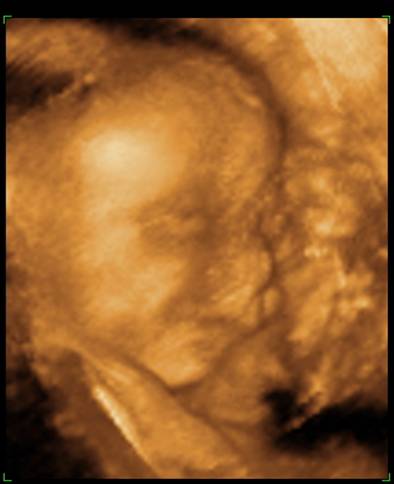

Voltunk 4D-n, rakok fel képeket mindjárt. (apja oda sem nézett, amikor mutatták az arcocskáját, csak nyavajgott, hogy mikor van már vége, érdemes volt elvinni...) De egyre kisebbnek mérik ezt a babát, és kezdek aggódni. Inkább 29 hetes méretei vannak, mint 30... És a súlya még mindig csak 1366, közben itt már mindenkinek minimum másfél kiló fölötti... :cry:

na, még ezeket megmutatom a kis pöttömről:

Kép

Boruska Fel a fejjel! Aludj egy jót! Embered biztos csak nyűgös volt, majd holnap biztos örömmel nézegeti édes kismanótokat a képeken. És miként sok okos már írta, a méretek csak átlagok, s ezek ugye a nagyobbakból és a kisebbekből tevődnek össze. Könnyebb megszülni egy 3 kg-os babát, mint egy 4,5 kg-t :) . És 1 hetes méret eltérés igazán semmitmondó. Valamint a súlybecslés az egyik legbizonytalanabb tényező, szóval ezen tényleg ne aggódj! Az utolsó képen én úgy látom mosolyog Berci. Álmodj ezzel a kis mosollyal!